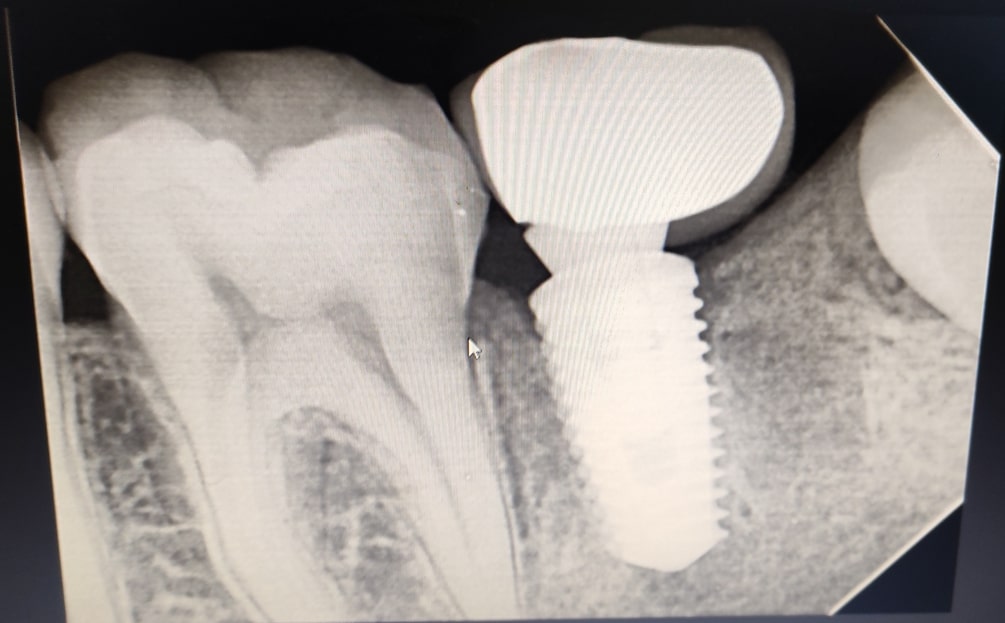

Dental implants are long-term investment in oral health. Unlike other tooth replacement options, such as dentures or bridges, dental implants can last a lifetime with proper care and maintenance. They do not require any special cleaning or adhesives, and they do not put strain on adjacent teeth like bridges can.